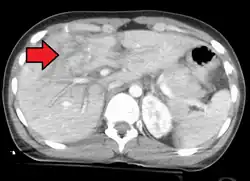

Imaging, such as the use of ultrasound or a computed tomography scan, is the generally preferred way of diagnosis as it is more accurate and is sensitive to bleeding, however; due to logistics this is not always possible.[6] For a person who is hemodynamically unstable a focused assessment with sonography for trauma (FAST) scan may take place which is used to find free floating fluid in the right upper quadrant and left lower quadrant of the abdomen. The FAST scan however may not be indicated in those who are obese and those with subcutaneous emphysema.[7] Its speed and sensitivity to injuries resulting in 400mL of free-floating fluid make it a valuable tool in the evaluation of unstable persons. Computed tomography is another diagnostic study which can be performed, but typically is only used in those who are hemodynamically stable.[7] A physical examination may be used but is typically inaccurate in blunt trauma, unlike in penetrating trauma where the trajectory the projectile took can be followed digitally.[8] A diagnostic peritoneal lavage (DPL) may also be utilized but has limited application as it is hard to determine the origin of the bleeding.[9] A diagnostic peritoneal lavage is generally discouraged when FAST is available as it is invasive and non-specific.[7]